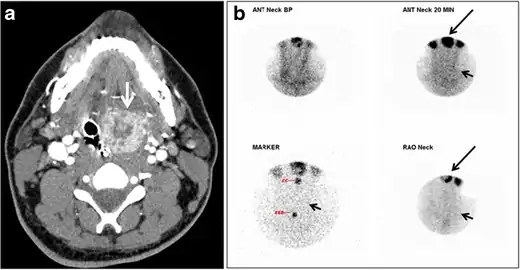

Fig. 17. Ectopic thyroid on the left parotid gland with a palpable left parotid mass in a 69-year-old male patient. a, b Axial and coronal enhanced neck CT scan demonstrates well-defined homogeneous enhancing mass (white arrows) within the left parotid gland with preserved surrounding fat planes. It also shows a normal thyroid in normal position in the lower neck. c Image taken 20 minutes after 5 mCi injected Tc99m-Pertechnetate shows normal thyroid uptake of tracer and physiological uptake in the salivary glands (short black arrow). There is a distinct focus of abnormal tracer accumulation in the left parotid/submandibular region. Patient was given lemon juice with evident normal washout from the salivary glands and relative retention by this abnormal focus (long black arrow).[1] Fig. 17. Ectopic thyroid on the left parotid gland with a palpable left parotid mass in a 69-year-old male patient. a, b Axial and coronal enhanced neck CT scan demonstrates well-defined homogeneous enhancing mass (white arrows) within the left parotid gland with preserved surrounding fat planes. It also shows a normal thyroid in normal position in the lower neck. c Image taken 20 minutes after 5 mCi injected Tc99m-Pertechnetate shows normal thyroid uptake of tracer and physiological uptake in the salivary glands (short black arrow). There is a distinct focus of abnormal tracer accumulation in the left parotid/submandibular region. Patient was given lemon juice with evident normal washout from the salivary glands and relative retention by this abnormal focus (long black arrow).[1]